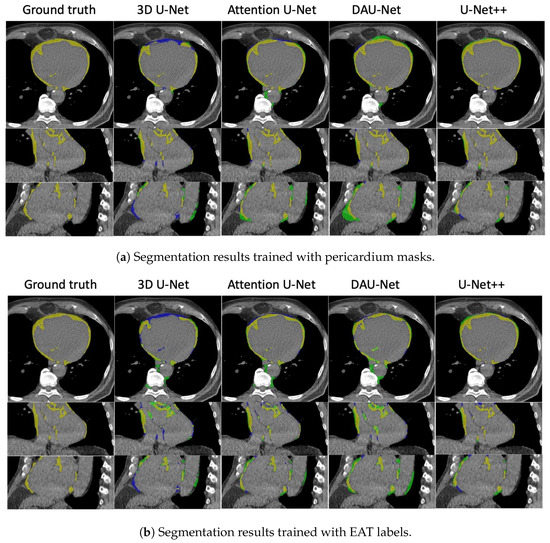

| Model | Label Type | DSC (%) | mIoU (%) | Sensitivity (%) | Specificity (%) | Correlation |

|---|---|---|---|---|---|---|

| 3D U-Net | Pericardium | 0.7588 | ||||

| EAT | 0.5648 | |||||

| 3D attention U-Net | Pericardium | 0.2085 | ||||

| EAT | 0.3883 | |||||

| DAU-Net | Pericardium | 0.8448 | ||||

| EAT | 0.8596 | |||||

| U-Net++ | Pericardium | 0.9123 | ||||

| EAT | 0.7303 |

| 3D U-Net | Pericardium | 0.6661 | ||||

| EAT | 0.6293 | |||||

| 3D attention U-Net | Pericardium | 0.5120 | ||||

| EAT | 0.1386 | |||||

| DAU-Net | Pericardium | 0.8445 | ||||

| EAT | 0.8047 | |||||

| U-Net++ | Pericardium | 0.9606 | ||||

| EAT | 0.9405 |